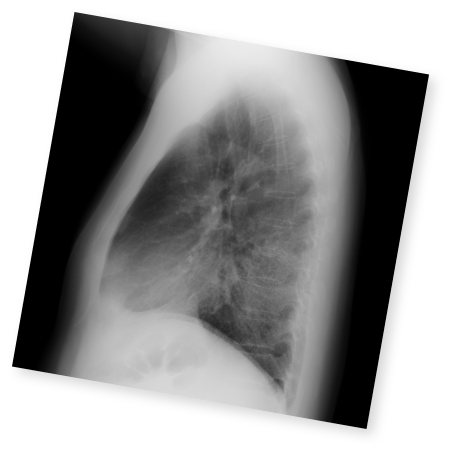

クイズで学ぶILDとILD-PH診断のポイント

実症例をもとに、画像や検査データから

間質性肺疾患および間質性肺疾患に伴う肺高血圧症の診断ポイントをクイズ形式で確認。

実践に即した診断力を養います。